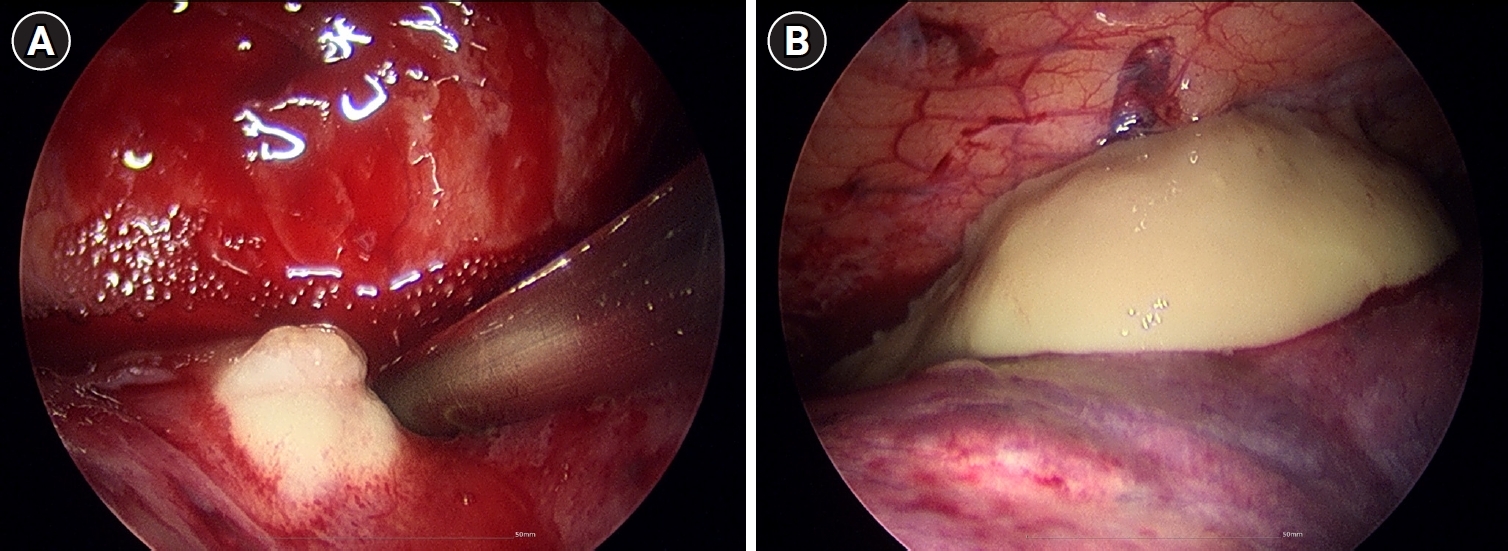

Empirical intravenous antibiotic therapy with piperacillin/tazobactam and levofloxacin was administered. On the second day of admission, the patient developed hemoptysis for which intravenous tranexamic acid was administered for 5 days, followed by oral maintenance. Clinical improvement was not achieved following a 7-day course of intravenous antibiotics, with the clinical course marked by unresolved febrile episodes and persistent leukocytosis. Furthermore, a follow-up chest CT on hospital day 7 revealed aggravation of the internal cavitations and abscess formation within the consolidative lesions of the right middle lobe and both lower lobes (Fig. 2). The failure of conservative management to arrest the necrotizing process, combined with the high risk of secondary sepsis from the poorly drained, inspissated purulent material, prompted the decision to escalate to video-assisted thoracoscopic surgery (VATS) for definitive source control and debridement. Intraoperative examination revealed dense pleural adhesions and extensive necrosis of the lung parenchyma. Thick, yellowish, and inspissated purulent material was drained from the abscess cavities located in the right middle and left lower lobes (Fig. 3). Given the deep and multiloculated nature of the abscesses, wide unroofing was performed via wedge resection using an endoscopic stapler and ultrasonic shear to ensure adequate drainage. Subsequently, thorough decortication and irrigation of the thoracic cavity were performed. A closed thoracostomy was performed with chest tube and Hemovac placement. Histopathological examination of the lung tissue revealed acute fibrinous and organizing pneumonia, consistent with chemical exposure.

Fig. 2.

Chest computed tomography on day 7 revealing multiloculated abscesses involving right middle and left lower lobes.

Fig. 3.

Intraoperative thoracoscopic findings of bilateral lung abscesses secondary to necrotizing pneumonia. (A) Right middle lobe. (B) Left lower lobe.

Fig. 2. Chest computed tomography on day 7 revealing multiloculated abscesses involving right middle and left lower lobes.

Fig. 3. Intraoperative thoracoscopic findings of bilateral lung abscesses secondary to necrotizing pneumonia. (A) Right middle lobe. (B) Left lower lobe.